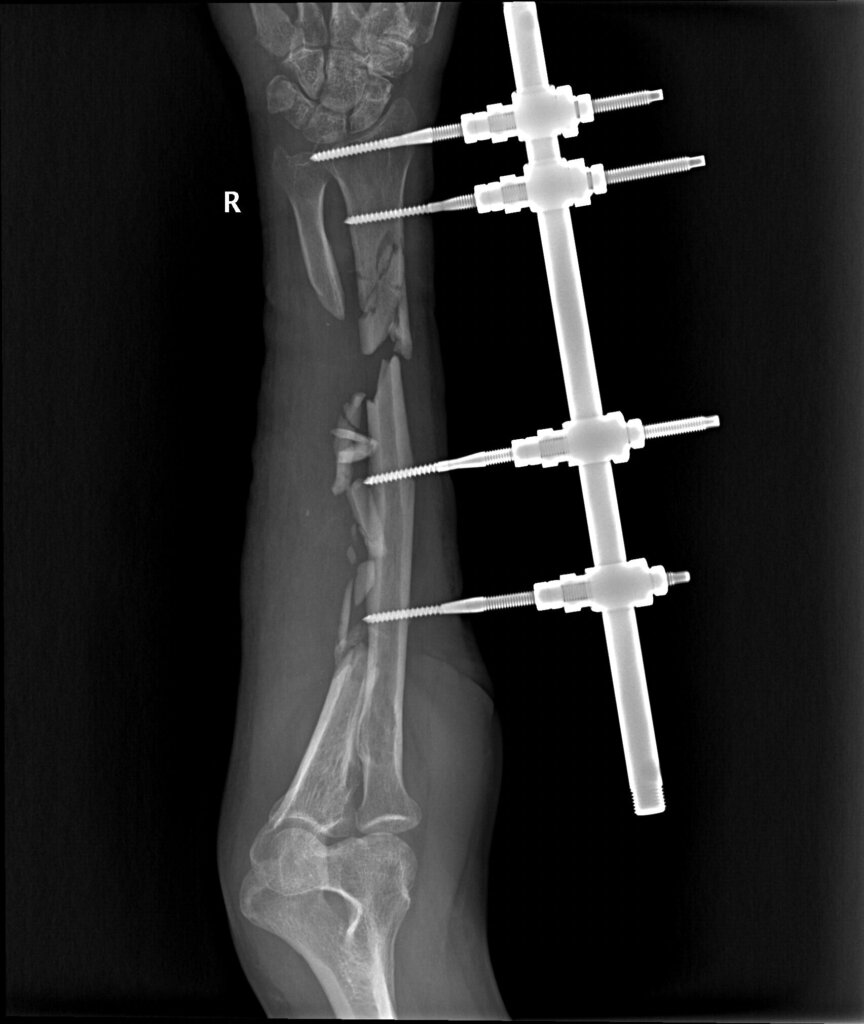

Согласно данным анамнеза и медицинской документации, пациент М. 49 лет получил огнестрельное осколочное ранение правой верхней конечности. Первая помощь оказана на месте. При поступлении в медицинский отряд пациенту выполнено рентгенологическое исследование правого предплечья. Выявлено: открытый многооскольчатый перелом нижней трети диафиза правой лучевой кости со смещением костных отломков, многооскольчатый перелом верхней и средней трети диафиза правой локтевой кости со смещением и дефектом костной ткани. Выполнена первичная хирургическая обработка ран правого предплечья и фиксация костей предплечья в АВФ КСВП1. На этапах эвакуации пациенту проводились этапные хирургические обработки до заживления ран предплечья.

На 5 сутки с момента поступления пациенту был выполнен демонтаж АВФ КСВП с правой верхней конечности, фиксация полимерной лонгетой от средней трети плеча до пястно-фаланговых суставов правой кисти.